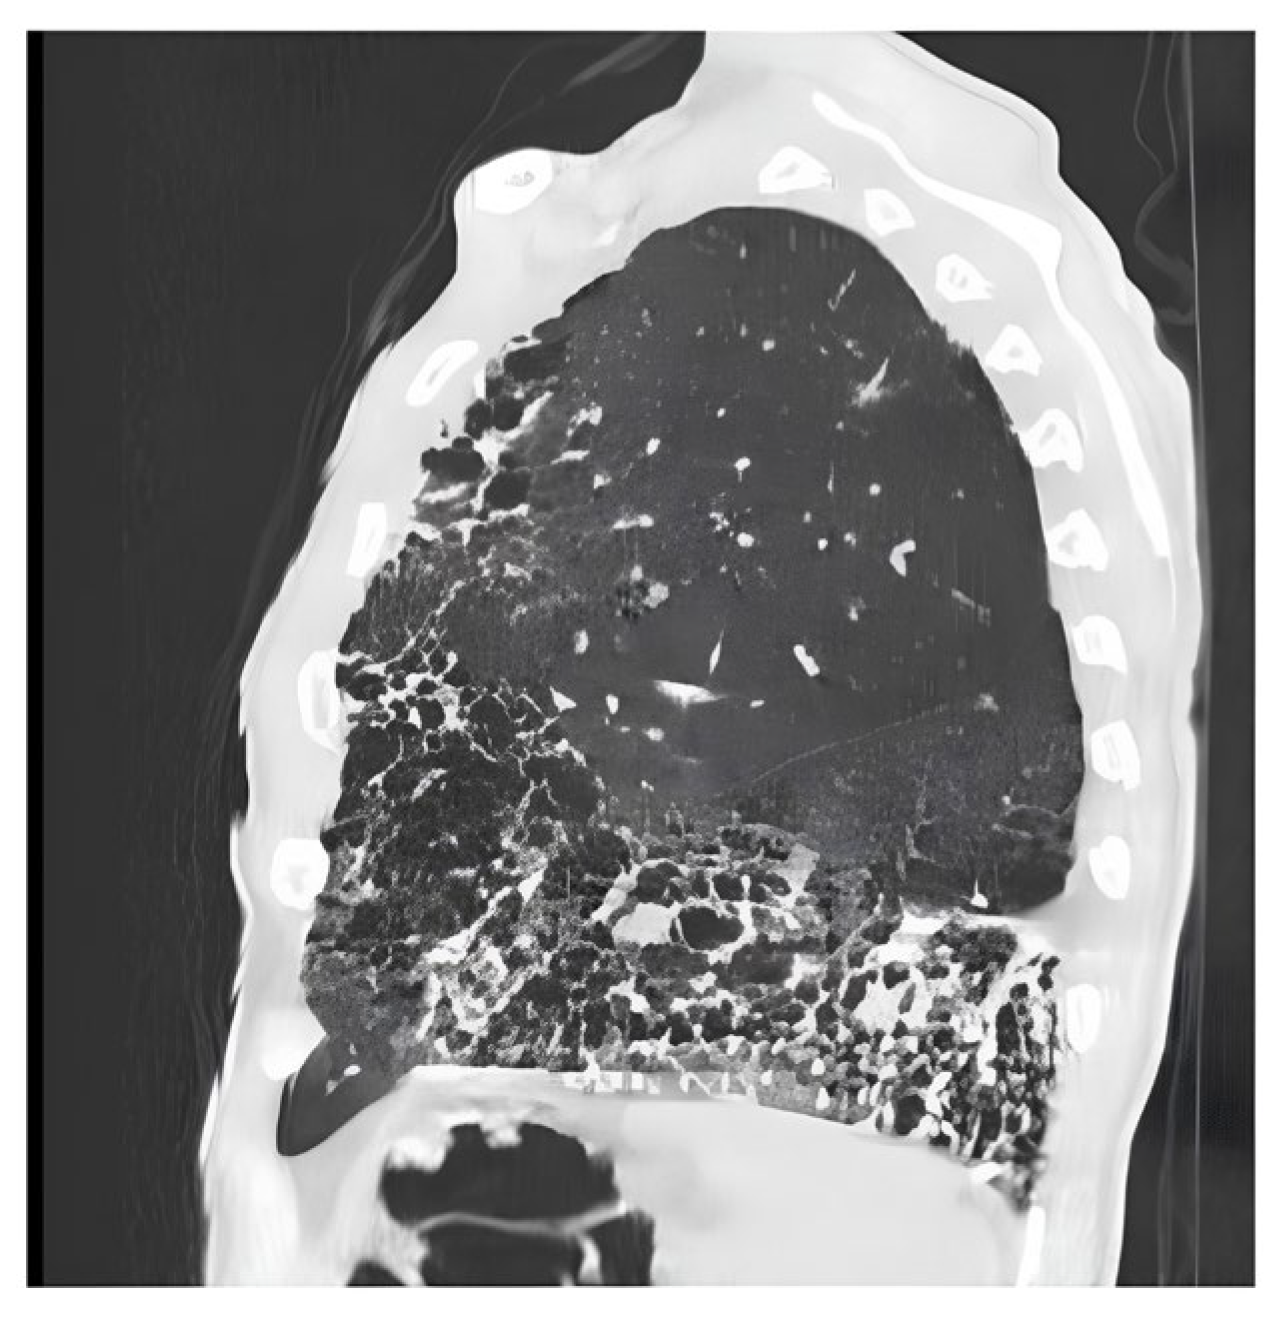

- Gaillard, F. Idiopathic Pulmonary Fibrosis. Available online: https://radiopaedia.org/cases/idiopathic-pulmonary-fibrosis-5?case_id=idiopathic-pulmonary-fibrosis-5 (accessed on 1 June 2025).